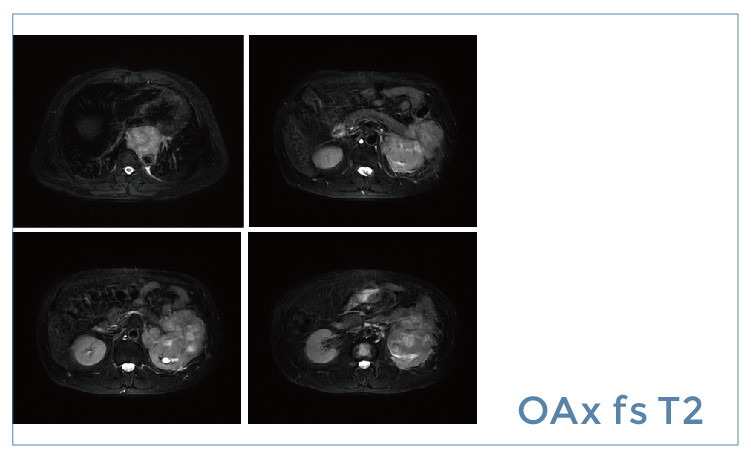

【朗润影像档案】20190510磁共振影像病例结果讨论